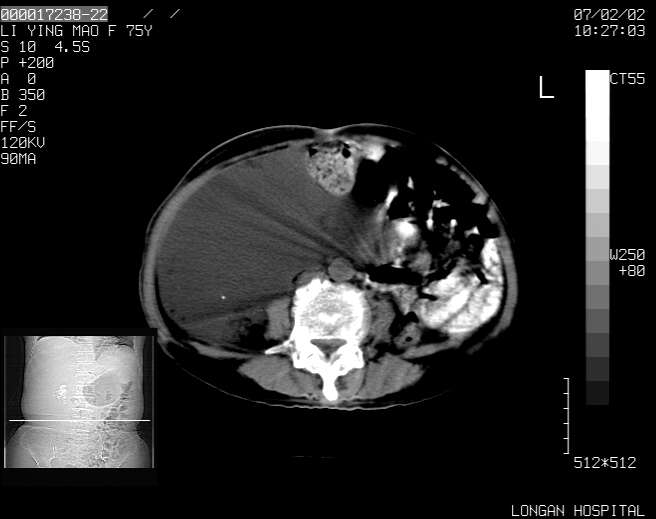

以下是引用dyqct在2007-2-10 8:53:00的发言:[br]考虑:1、肝脏多发囊肿[br] 2、左肾囊肿,右肾多发结石并积水。[br] 3、右胸少量积液。[br] 4、右肾周包裹性积液或淋巴管瘤(有见缝就钻的征象、薄隔、小结节状钙化)?[br] 5、腰椎动脉瘤样骨囊肿?[br] [br] [br]